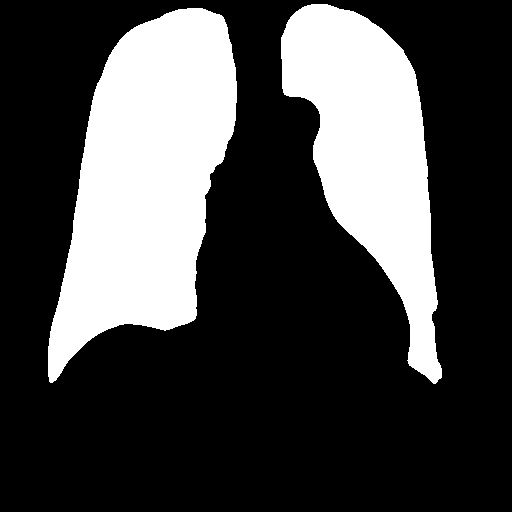

After heart and lung masks are computed, we performed dilation followed by erosion to fill holes in output mask [18], then we find the connected components of prediction masks (Figure 3).

From the lung mask, we chose the two largest connected components and disregarded others as noise. The connected component with a lower x-axis coordinate is designated as the left lung mask and the other as the right lung mask. From the heart mask, we chose the connected component larger than a given threshold and closest to the center and designate it as the heart mask.